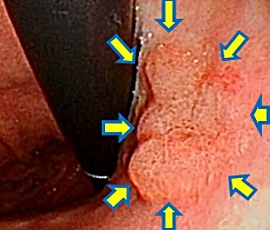

粘膜下層剥離

剥離終了